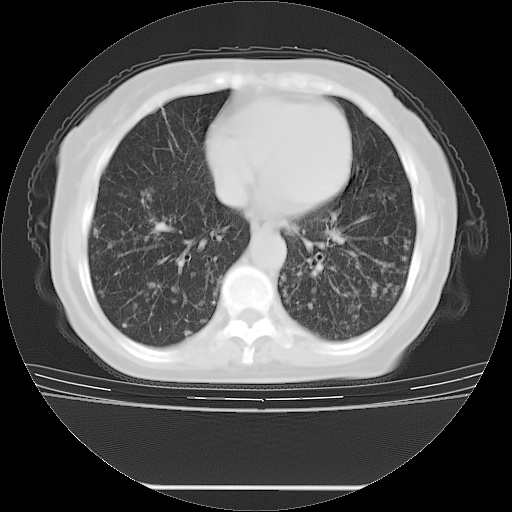

患者女性,72岁,慢性咳嗽3月余,曾抗炎治疗无效果,最近抗结核治疗约半月余,症状缓解。

ct示两肺粟粒状病灶,以两肺上叶尖后段及下叶背段分布为主;首先考虑结核。请战友们分析。

考虑 1 弥漫性泛细支气管炎, 2 结核不除外/.  有小叶中心结节 和 树芽征!!

两肺内病灶呈小结节状和树芽状,纵膈的肿大的淋巴结密度不均匀,并见有钙化,考虑为两肺结核可能更大些。

两肺内病灶呈小结节状和树芽状,纵膈的肿大的淋巴结密度不均匀,并见有钙化,多形态病灶,考虑为两肺结核,肝内考虑小囊肿。

病灶以结节为主,大部分边界清楚,分布不均,病灶形态较单一,偶见空泡征,纵膈淋巴结肿大钙化,无结核中毒症状考虑 感染性病变【真菌类可能性大】,细支气管肺泡癌。其他待排

纵隔见肿大淋巴结并钙化,首先考虑结核,但感觉小结节像“挂果”征,分布位于支气管边缘,所以不排外肺泡癌,建议抗唠后复查吧?不然是癌的话,也不好治吧?化疗?